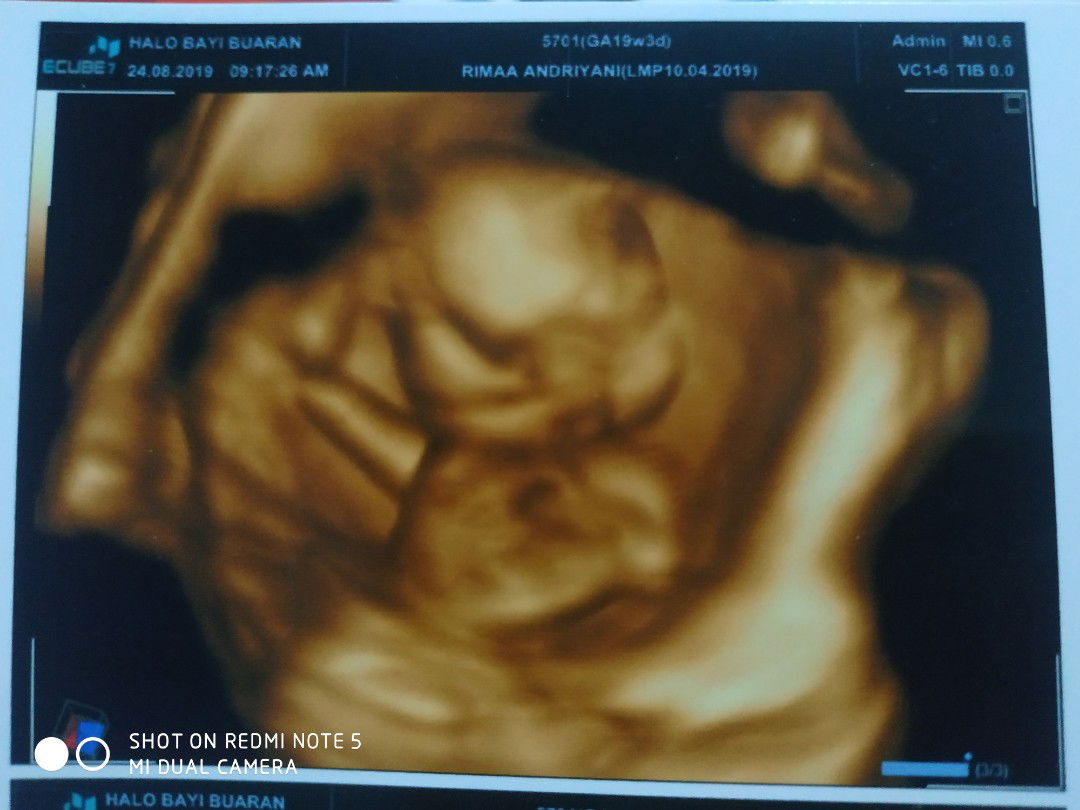

Assalamualaikum smua nya saya mau cerita dikit nih, saya sekarang hamil 19w dan kemaren hari sabtu saya pertama kali nya di usg dan dokter bilang bayi saya belom berenang bebas kaya masih diem jja gtu trus air ketuban nya juga kurang dan dokter bilang lagi klo usia kandungan saya itu bukan 19w tapi kaya baru 16w tapi lucu nya posisi bayi saya kaya santai bgd tangan dikeatasin gitu hehehe? terus dokter juga blg klo jenis kelamin bayi saya laki" dan saya malah bingung kenpa usia sgtu cepet bgd keliatan jenis kelamin ampe kluarga dan temen" saya juga pda bingung hehehehehe? tapi minta doa jja ya buat smua bunda dsni smoga bayi nya sehat dan tidak ada masalah amin